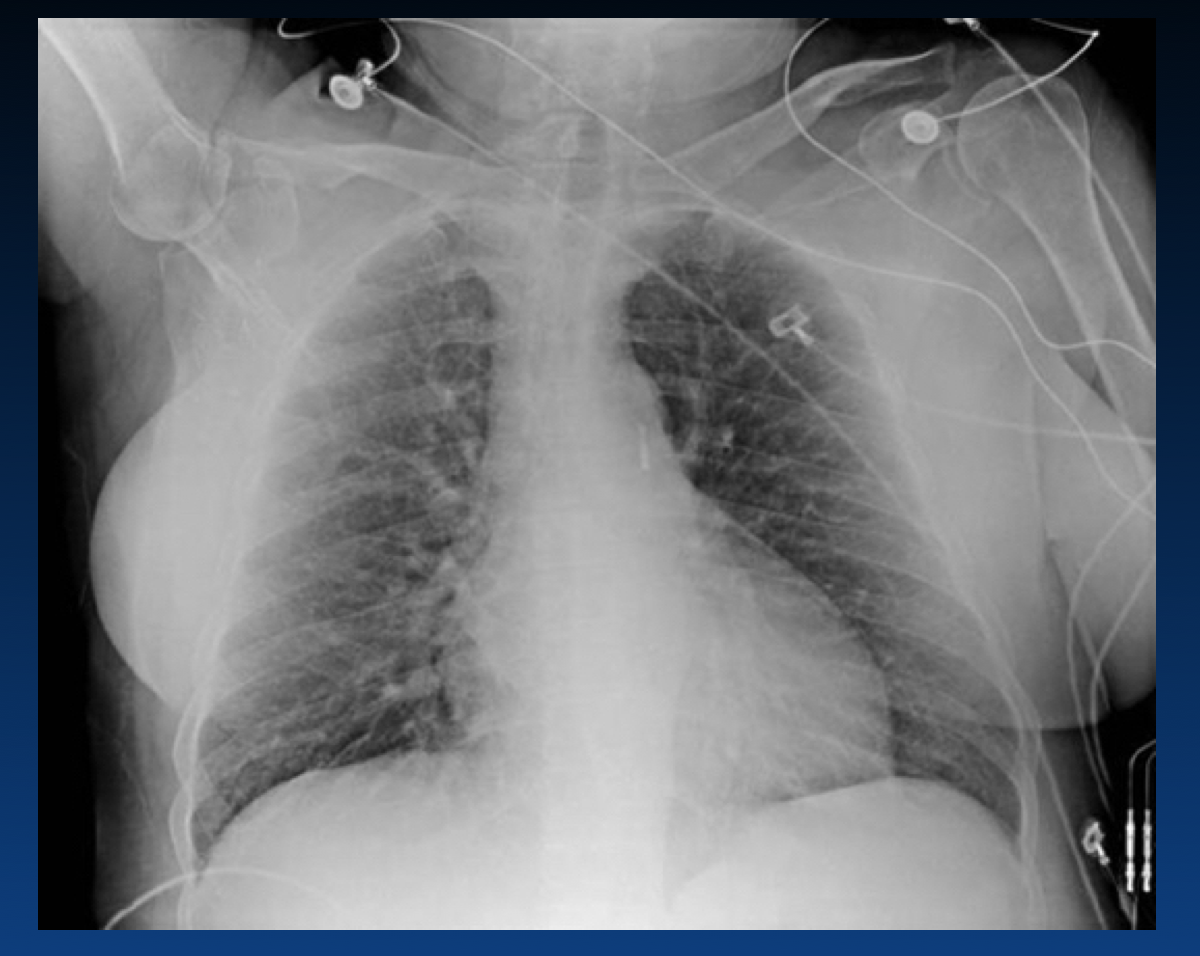

What is shown here?

What are the features of right heart strain from pulmonary embolism?